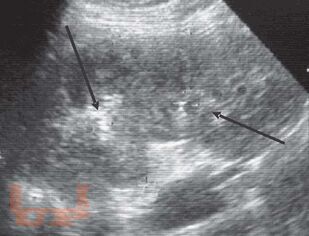

Монография посвящена применению лучевых методов исследования в ранней диагностике острого пиелонефрита. Систематизированы лучевые симптомы заболевания, на основании применения рентгенологического и ультрасонографического методов, а также метода компьютерной томографии. Представлена лучевая семиотика различных форм гнойного пиелонефрита (апостематоз, карбункул, абсцесс). Показана динамика изменений воспалительного процесса в паренхиме почек в процессе лечения. Данное практическое руководство будет интересно врачам лучевым диагностам, терапевтам, урологам, хирургам, а также студентам медицинских вузов.